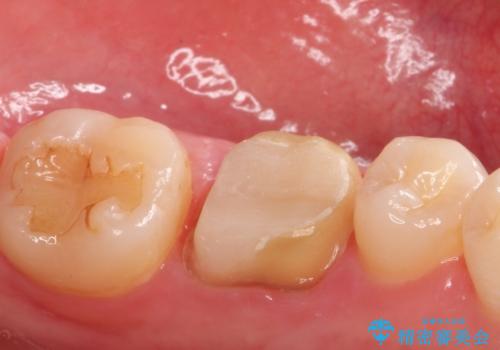

- 下の奥歯の銀歯を白くしたいとのことで来院されました。

痛みなどの症状はなく、前に根管治療を行っている歯になります。

古い銀歯を除去し、審美性の良いセラミッククラウンでの治療を行うこととしました。